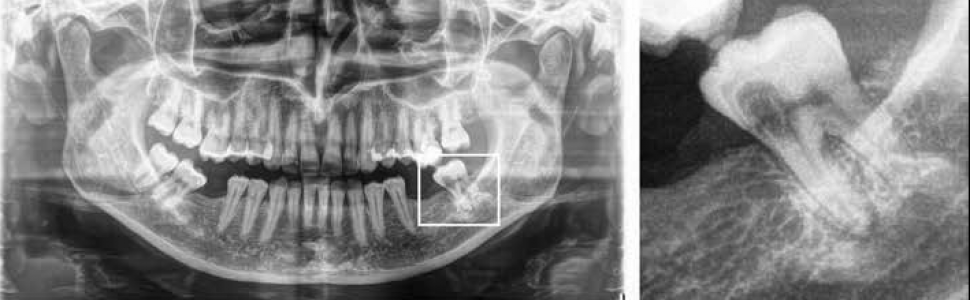

Kobieta, lat 45, odczuwała dolegliwości związane z zębem 37. Okresowo występował samoistny ból, który mijał. Pacjentka wyczuwała nieprzyjemny zapach w tej okolicy. Ząb wyglądał na nietknięty procesem próchnicowym, jedynie guzek policzkowy bliższy miał inne zabarwienie. Po odsłonięciu brzegu dziąsła zgłębnikiem odnaleziono niewielki otwór. Wykonano zdjęcie pantomograficzne, które uwidoczniło charakterystyczny obraz. Diagnoza – inwazyjna resorpcja przyszyjkowa.